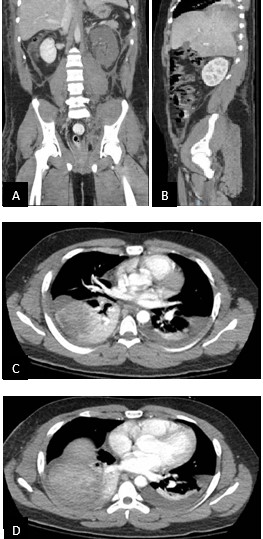

On day 6, the patient was extubated. However, he became increasingly hypoxic and tachypneic over the course of the next day. A CT of the chest and pelvis was conducted ([Figure 2]). There was no pulmonary embolism nor pneumothorax, but instead, the right lobe of the liver appeared to be bulging into the right hemithorax; a delayed right post-traumatic diaphragmatic hernia was diagnosed. This finding and the continued left kidney vascular abnormality were indications for an exploratory laparotomy.